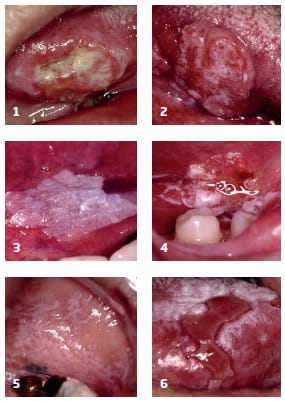

What Does Mouth Cancer Look Like 5 Pictures Of Mouth Cancer

Visual Guide To Oral Cancer

What Does Mouth Cancer Look Like 5 Pictures Of Mouth Cancer

Oral Cancer Images The Oral Cancer Foundation

Oral Cancer Images The Oral Cancer Foundation